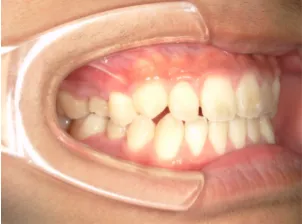

小学5年生の出っ歯、過蓋咬合の治療

治療前①小5:スタート

| はじめのご相談 | 凸凹になりそうと一般歯科の先生に言われたのでみてほしい |

|---|---|

| カウンセリング・診断結果 | 下あごが後退しているタイプの出っ歯で、過蓋咬合で下あごが前に成長しにくいタイプの顔立ちです。 上の歯列弓が小さめで前歯に凸凹があります。 口元が閉じにくい口唇閉鎖不全があります。 *上記に対する治療の流れを説明し(拡大・前歯の並べ替え→出っ歯の改善→モノブロック装置(筋機能的咬合誘導装置)→必要によりマルチブラケット法)、以下の治療を提案しました。 |